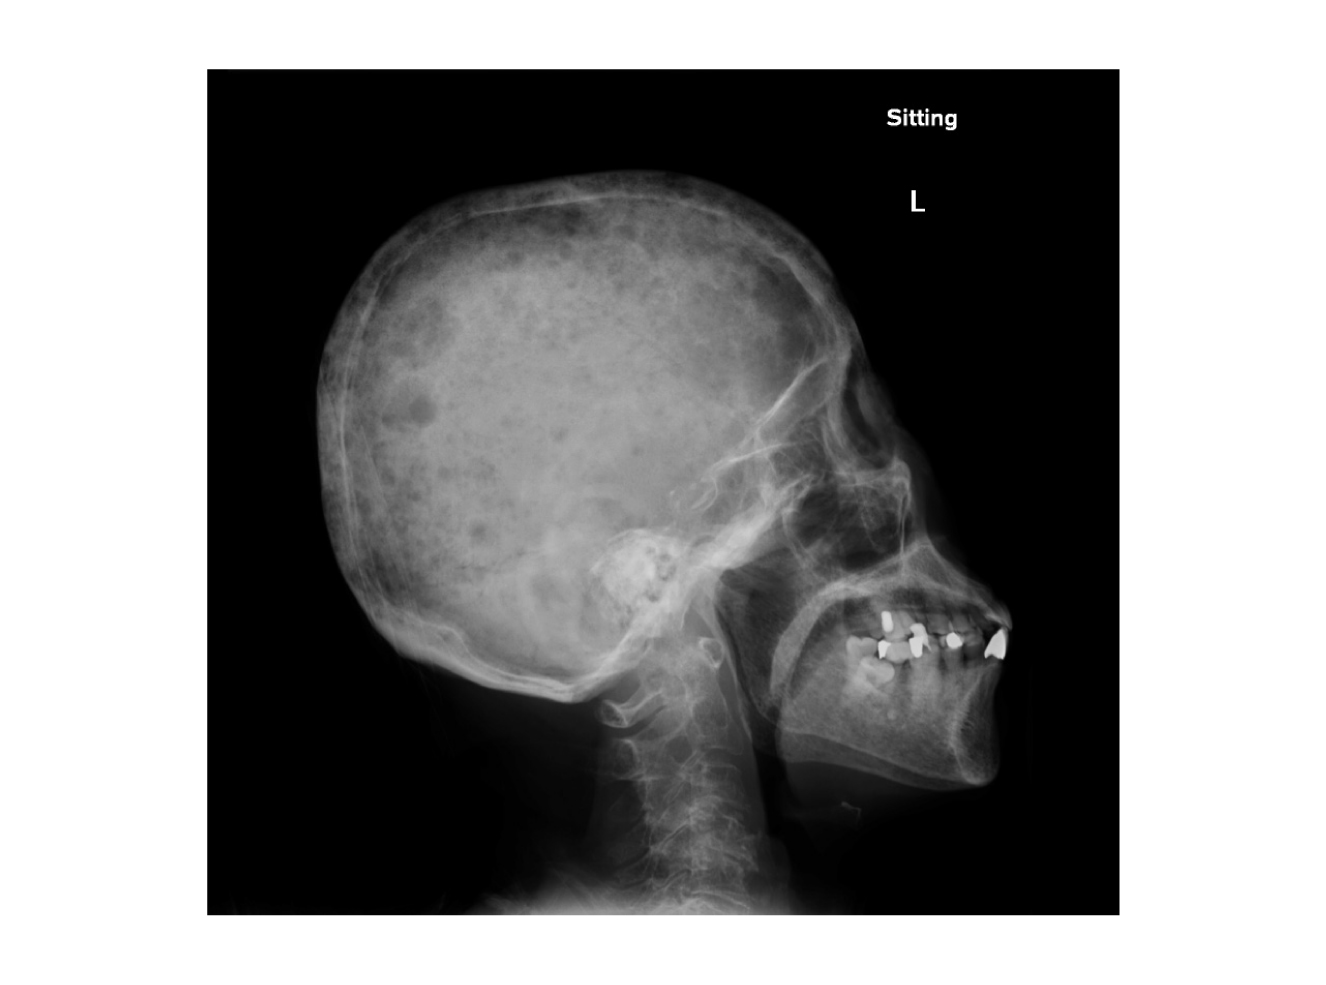

Dr. Wong shared one case of the use of oral MM therapy in a NDMM transplant-ineligible patient during the pandemic with an uptick of COVID-19 cases. “The patient was an old lady aged 83 years with several comorbidities including hypertension, diabetes and hyperlipidaemia. She presented with severe pneumonia requiring intensive care and the blood tests showed pancytopenia. Further investigations showed an IgA kappa protein of 13 g/L and a bone marrow examination confirmed the diagnosis of multiple myeloma. She had hypercalcaemia, multiple lytic bone lesions (Figure 2) and anaemia (a haemoglobin level of 6.3 g/dL). Treatment options including proteasome inhibitor and IMiD-based treatment were offered to her,” pointed out Dr. Wong.

Figure 2.

Skull X-ray of a NDMM transplant-ineligible patient